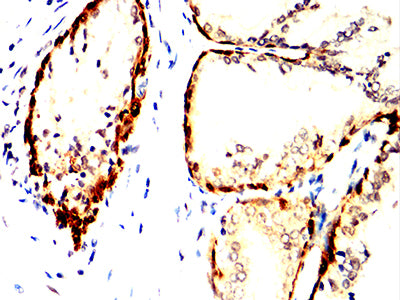

Immunohistochemical analysis of paraffin-embedded human prostate cancer tissues using ACHE mouse mAb with DAB staining.